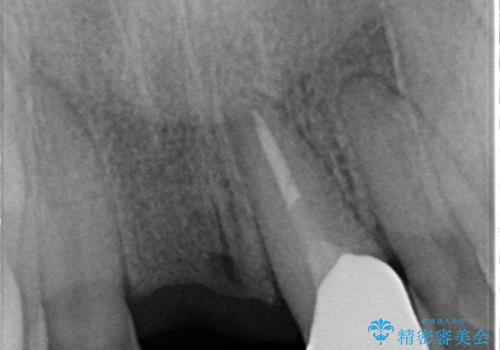

【オールセラミックスタンダード】前歯のブリッジ

- 矯正治療終了後の患者様です。

前歯が欠損しており、ブリッジでの修復を希望されましたので、オールセラミッククラウン(スタンダード)で治療を行いました。